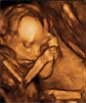

El bebé casi saca la lengua en el bostezo.